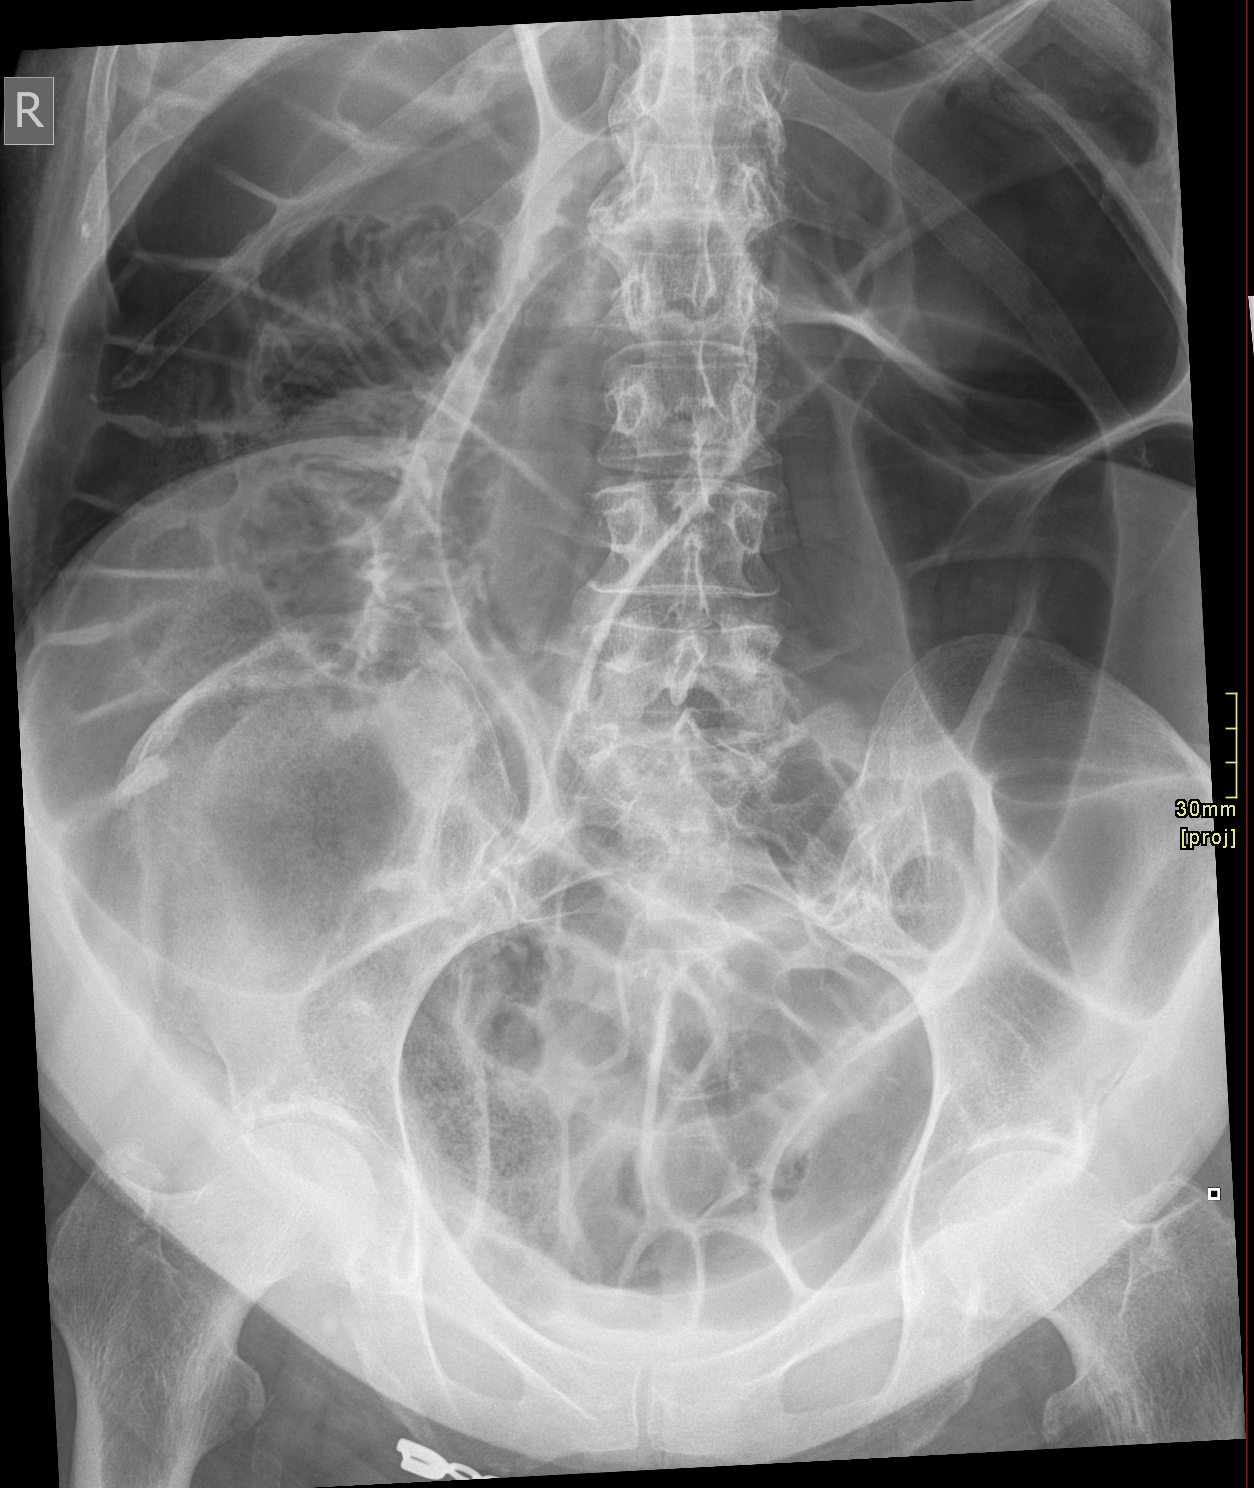

3. Sigmoid Volvulus